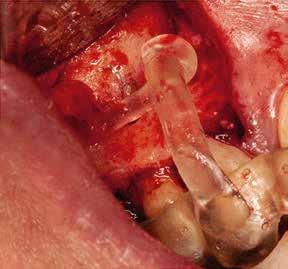

CÉLZOTT ENDODONCIAI MIKROSEBÉSZET

1. a-n. ábrák: Preoperatív CBCT-felvétel a bal alsó 6-os (3.6) fogról. Az axialis (a), coronalis (b) és sagittalis (c) nézeteken a mezialis és distalis gyökerek apicalis harmada körül sugáráteresztő zóna és ép buccalis corticalis csont látható. Egy olyan sablont terveztünk, amely jelezte a csontablak határait az apicalis terület pontos elérése érdekében (d). A mikrosebészeti bevatkozás során a sablont a helyére illesztettük (e), a csontablak határait megjelöltük (f) egy Piezotome CUBE LED kézi-darabba fogott fűrésszel, majd kivágtuk és eltávolítottuk (g és h) az apicalis területhez történő hozzáférés, illetve a mezialis és distalis gyökerek rezekciójának, retrográd preparációjának és retrográd gyökértömésének elvégzése érdekében (i). Végezetül a csontablakot visszaillesztettük és kollagén szivaccsal stabilizáltuk (j). A műtét után közvetlenül készített röntgenfelvétel a 3.6-os fogról (k). A kétéves kontroll során készített CBCT-felvétel: axialis (l), coronalis (m) és sagittalis (n) nézetek.

Esetbemutatás (1.)

Egy 63 éves páciens korábban már kezelt bal alsó első nagyőrlőfogából (3.6) eredő mérsékelt fájdalom miatt kereste fel rendelőnket. A kórtörténetében panasza szempontjából releváns információ nem szerepelt. Az elkészült CBCT-felvételen a korábbi kezelések során észre nem vett, jelenleg feltáratlan meziobuccalis csatornát, valamint a mezialis és distalis gyökerek körül kialakult periapicalis elváltozást, és ezt a léziót borító intakt buccalis corticalis csontlemezt láttunk.

A fog revideálását és újbóli gyökértömését két ülésben végeztük el. A régi gyökértömés eltávolítását, valamint mindhárom gyökércsatorna megmunkálását és fertőtlenítését követően kalcium-hidroxid alapú gyógyszeres zárást helyeztünk a gyökércsatornákba. A gyökértömés egy héttel később került behelyezésre. A páciens panaszai két hónap elteltével sem szűntek.

Klinikai vizsgálat során vertikális kopogtatási érzékenységet jelzett. A fog körül mérhető szondázási mélység és a fogmobilitás fiziológiás volt. A CBCT-felvételen nem észleltünk a csontos regeneráció megindulására utaló jeleket (1. a–c. ábrák). A korábban gyökérkezelt, gyökértömött és revideált 3.6-os fog esetében az alábbi diagnózis került felállításra: periodontitis periapicalis symptomatica. A panaszokat okozó fog további ellátása során navigált endodonciai mikrosebészetet kívántunk alkalmazni. Az alsó állcsontról intraorális szkent (TRIOS, 3Shape) készítettünk, és a felszíni topográfiát tartalmazó STL fájlt, valamint a CBCT-felvétel készítése során nyert DICOM fájlokat a Blue Sky Bio szoftver segítségével egyesítettük. A sebészi sablon megtervezésére az így kapott háromdimenziós képet használtuk. A sablon kialakítása során arra törekedtünk, hogy a sablon egyértelműen meghatározza a gyökércsúcsi terület eléréséhez szükséges csontablak határait (1. d. ábra)

A beavatkozás során helyi érzéstelenítésben teljes vastagságú mucoperiostealis lebenyt képeztünk, és a sablon segítségével bejelöltük a preparálandó csontablak határait. Az ablak széleinek megfelelően Piezotome CUBE LED kézi-darabbal (ACTEON) a kortikális teljes vastagságában vágást ejtettünk, majd az így kapott csontlemezt (ablakot) eltávolítottuk (1. e–h. ábra), és ezt követően steril fiziológiás sóoldatba helyeztük. A rezekció elvégzését követően (1. i. ábra) a mezialis csatornákat ultrahangos eszközök segítségével (NSK) retrográd irányból preparáltuk, majd az így kialakított mélyedésbe retrográd gyökértömést készítettünk. A tömés anyagául az EndoSequence BC RRM Fast Set Putty-t (Brasseler) választottuk. A tömés elkészítését követően a csontablakot visszaillesztettük, és a stabilizálása érdekében a vágásoknak megfelelően kialakult résekbe kollagén szivacsokat (Collagen Tape, Zimmer Biomet) helyeztünk (1. j-k. ábra). A lebenyt 6/0-s Prolene varratokkal (Corpaul) rögzítettük.

A kétéves kontroll során elvégzett klinikai és radiológiai vizsgálat (CBCT-felvétel) a periapicalis elváltozások megszűnését és a corticalis csontállomány tünet- és szövődménymentes gyógyulását